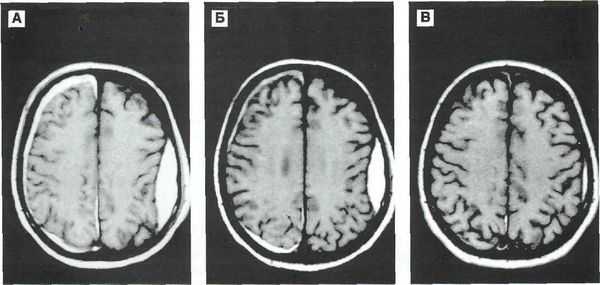

Современные методы нейровизуализации позволяют не только диагностировать внутримозговую гематому, но и выявить причину ее появления. Ведущим диагностическим методом являются:

- КТ головного мозга. Как правило, на томограммах внутримозговая гематома имеет вид очага гомогенной плотности округлой или овальной формы. Если гематома сформировалась в результате ушиба головного мозга, то она обычно имеет неровный контур. С течением времени происходит уменьшение плотности гематомы до изоплотного состояния, при котором ее плотность соответствует плотности мозговой ткани. Для малых гематом этот период составляет 2-3 недели, а для средних — до 5 недель.

- МРТ головного мозга. При уменьшении плотности гематома лучше визуализируется при помощи МРТ, хотя в начальном периоде применение МРТ может привести к ошибочному диагнозу в пользу опухоли с кровоизлиянием. Поэтому, при наличие такой возможности, многие неврологи и нейрохирурги предпочитают использовать в ходе диагностики оба способа нейровизуализации (КТ и МРТ).